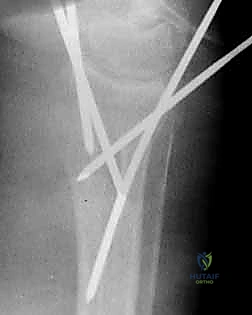

4. إدخال الأسلاك المعدنية (Pinning)

باستخدام مثقاب جراحي كهربائي دقيق، يقوم الدكتور هطيف بإدخال السلك المعدني الأول عبر الجلد، مروراً بالعظم السليم، ثم يعبر خط الكسر ليصل إلى الشظية المكسورة ويثبتها.

هناك عدة تقنيات هندسية لإدخال الأسلاك، أشهرها:

* تقنية كابانجي (Kapandji Technique): إدخال الأسلاك مباشرة في خط الكسر واستخدامها كرافعات لرفع العظم المنخسف ثم دفعها في العظم المقابل لتثبيته. يتميز الدكتور هطيف ببراعة فائقة في تطبيق هذه التقنية المعقدة.